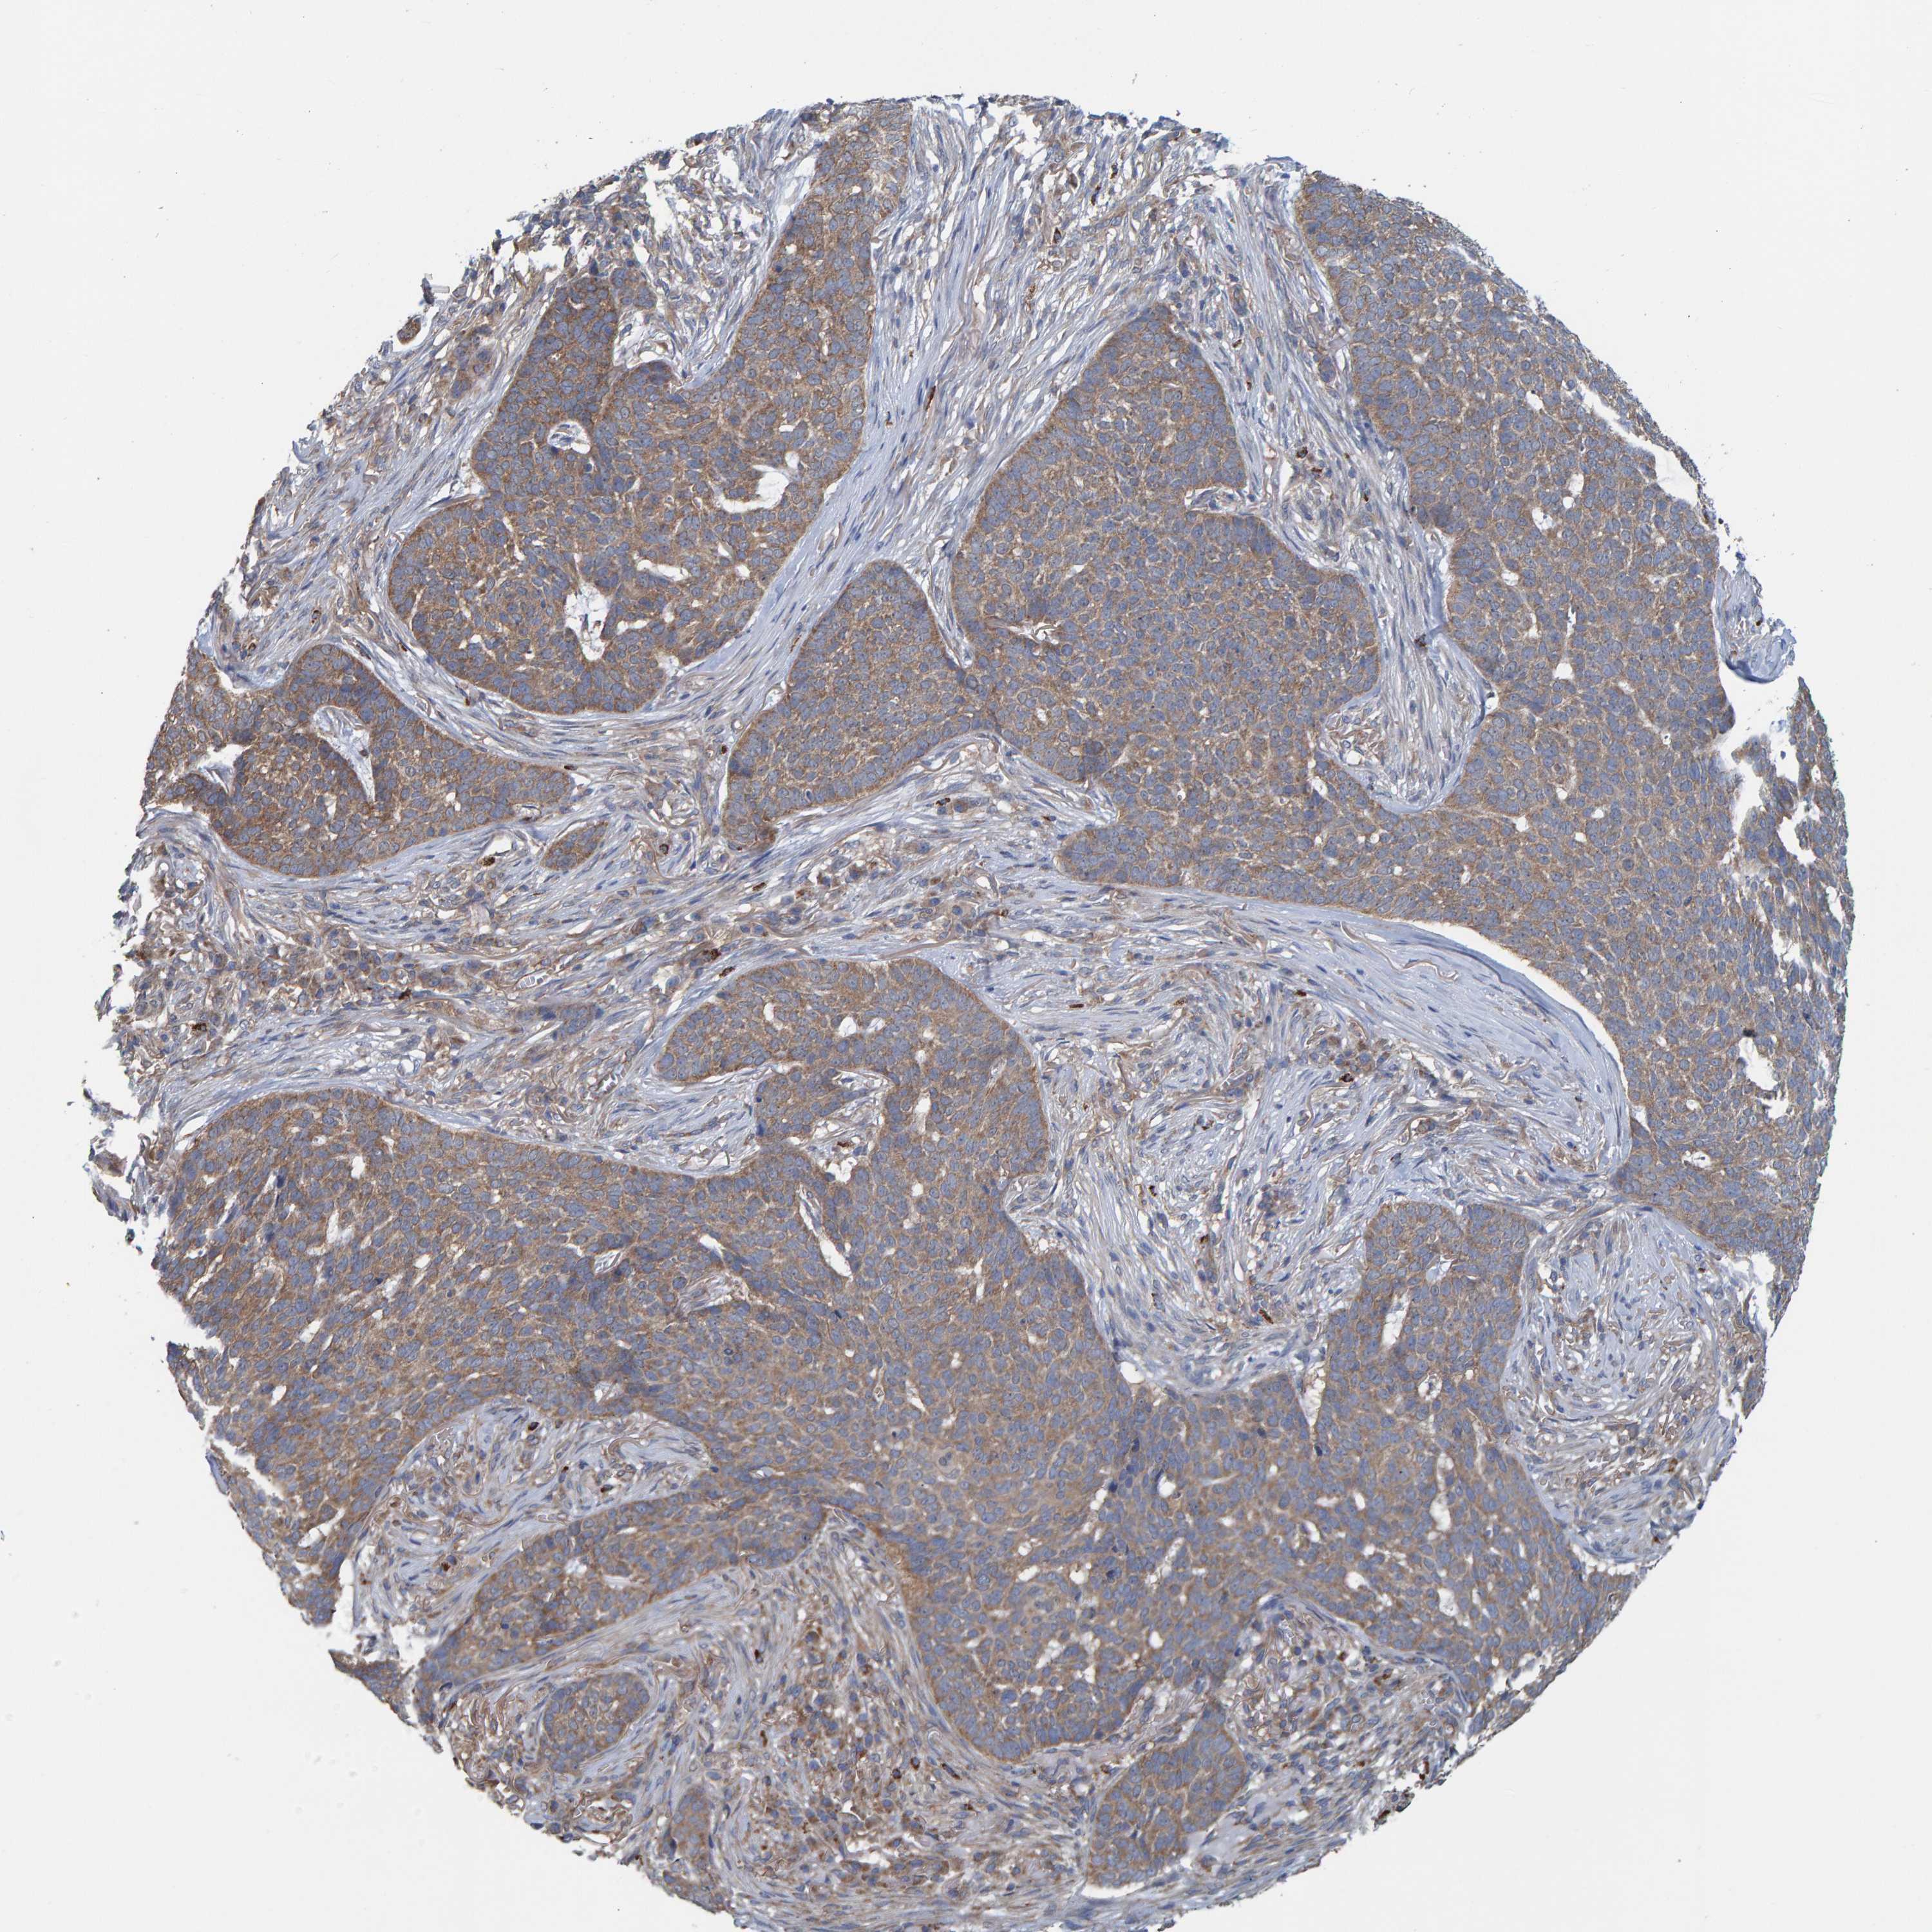

SKIN CANCER - Protein expressioni

A mouse-over function shows sample information and annotation data. Click on an image to view it in a full screen mode. Samples can be filtered based on level of antibody staining by selecting one or several of the following categories: high, medium, low and not detected. The assay and annotation is described here.

Each image is clickable and will lead to virtual microscopy that enables deeper exploration of all samples and also displays staining intensity scores, fraction scores and subcellular localization as well as patient and tissue information for each sample.

Antibody HPA021403

Antibody HPA021844

Antibody CAB037304

Staining

High

Medium

Low

Not detected

Intensity

Strong

Moderate

Weak

Negative

Quantity

>75%

75%-25%

<25%

None

Location

Nuclear

Cytoplasmic/membranous

Cytoplasmic/membranous,nuclear

Basal cell carcinoma

Squamous cell carcinoma, NOS

Squamous cell carcinoma, metastatic, NOS

Squamous cell carcinoma in situ, NOS

Adnexal tumor, benign